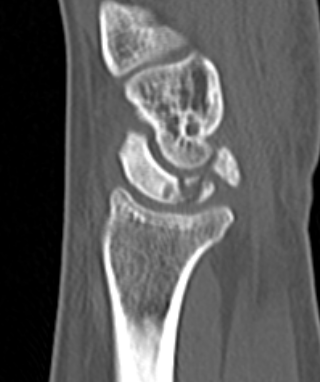

CT

Hesse et al J Hand Surg Eur 2025

- CT more accurate at gauging Kienbock's

- disease frequently worse on CT than assessed on xray

Lunate precollapse

CT demonstrating lunate fragmentation and collapse